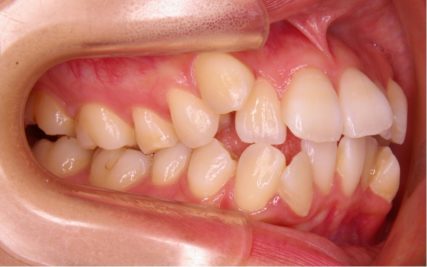

でこぼこ/20代女性

- 不正咬合/叢生(でこぼこ)

- 治療前

- 上下とも前歯のスペース不足が認められた。歯のサイズと顎の幅とのバランスが不調和な事が原因の1つとして考えられる。

- 治療後

- 前歯部のでこぼこが解消され、正常咬合を獲得する事が出来た。又、歯科矯正用アンカースクリューを用いる事で抜歯スペースを有効に利用できた。